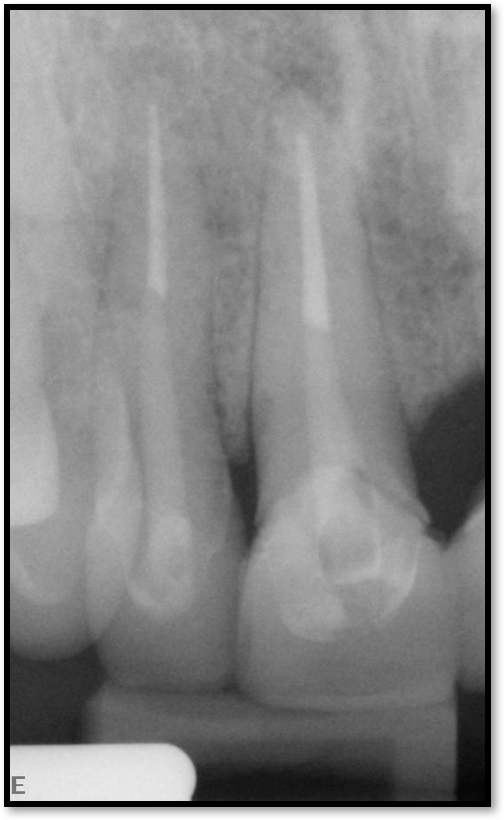

As to which material to use, the literature indicates fiber is better because it has greater flexibility and is less likely to allow for vertical fractures.2,3 It also has better esthetics, which is significant for both anterior and posterior teeth. The problem with fiber posts is that they can snap off and pull out. When they snap off, they are difficult to remove. A tapered diamond bur or ultrasonic can be used, but it must be done very carefully. Depending on the circumstances, metal can also be difficult, but metal is often serrated or threaded and can be unwound with an ultrasonic. However, fiber is significantly more flexible because it has a better modulus of elasticity, which should be as close to the dentin's elasticity as possible. On the radiograph, it can be difficult to see. Figure 17 shows a case with a good fiber post on the lateral that could be longer. The central should definitely be longer than it is. Because the clinician thought the posts and crowns were well done with good seals, when the patient had pain and apical radiolucencies, they were treated with apicoectomies. This was easier and less invasive than dismantling the previous structure.

Fig 17. A case with a good fiber post on the lateral that could be longer.

Figure 17